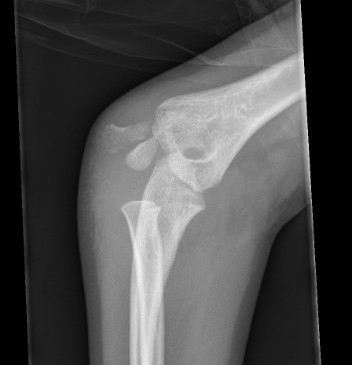

Open reduction of displaced lateral condyle in left elbow

Open reduction and K wires / screw fixation

AO surgery reference lateral approach distal humerus

Lateral approach to distal humerus

- curved incision over lateral supracondylar ridge of humerus, and over proximal radius

- proximally intermuscular interval between brachioradialis & triceps

- proximally elevate brachioradialis and ECRL off the distal humerus

- distally split common extensor origin between ECRB and EDC and elevate anteriorly

Don't dissect posteriorly to protect blood supply

Don't need to dissect distal fragment

Use anterior homan retractor across distal humerus to elevate anterior capsule

- visualize distal joint line and perform anatomical reduction under vision

- one K wire parallel to joint surface across fracture into trochlea

- one K wire at 45 degrees to first engaging medial metaphysis

- bury K wires as need to be in for 6 weeks